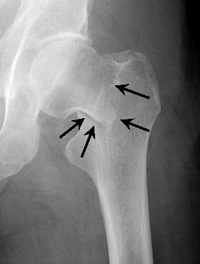

Intracapsular Fracture. This fracture occurs at the level of the "neck" of the bone and may have loss of blood supply to the bone.

Repair of an intracapsular fracture with individual screws.

Repair of an intracapsular fracture with a single compression hip screw.

For true intracapsular hip fractures, the surgeon may decide either to fix the fracture with individual screws (percutaneous pinning) or a single larger screw that slides within the barrel of a plate. This compression hip screw will allow the fracture to become more stable by having the broken area impact on itself. Occasionally, a secondary screw may be added for stability.

If the intracapsular hip fracture is displaced in a younger patient, a surgical attempt will be made to reduce, or realign, the fracture through a larger incision. The fracture will be held together with either individual screws or with the larger compression hip screw.